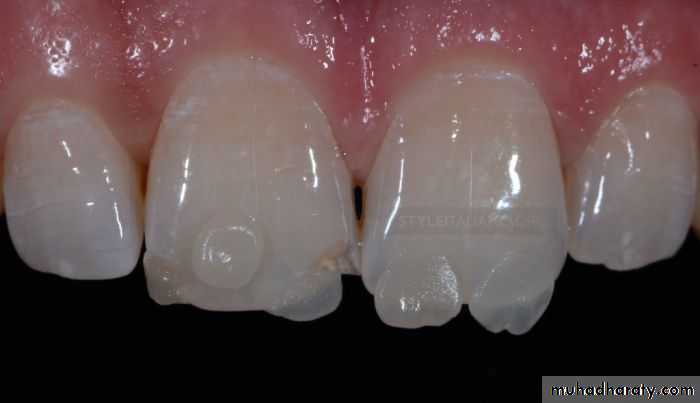

3. Voids

Causes of voids include:1. Mixing of self-cured composites.

2. Spaces left between increments during insertion.3. sticky composite pulling away from the preparation during insertion.

Potential solutions include:

1. More careful technique.2. Repair of marginal voids by preparing the area and rerestoring.